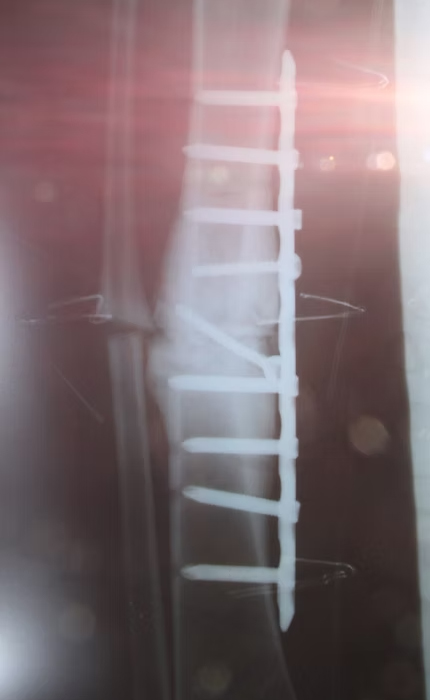

Ein anschauliches Beispiel ist dieser 25-jährige Mann, der sich beim Fußballspielen ein Bein brach. Aufgrund der nicht vorhandenen Versorgung solcher Verletzungen in Sierra Leone war das Bein, wie gut zu sehen ist, völlig schief zusammengewachsen.

Nach der gelungen Operation wird der Patient wieder im Stande sein, ein normales Leben zu führen, zu arbeiten und eine Familie zu ernähren.